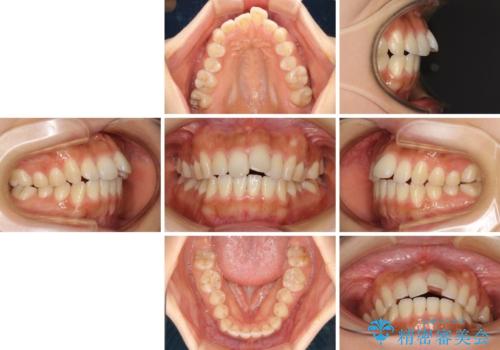

- 飛び出した前歯と口元の突出感を気にして来院された患者様です。

奥歯の咬み合わせを見ると、上顎が下顎に対して相対的に前方にありました。

口元の突出感を改善するためには、上顎臼歯を後方に移動させた咬み合わせにする必要があります。

インビザライン単体で改善することも可能ですが、達成する可能性が高くないため、カリエールディスタライザーという補助装置を併用して、より確実性を上げることとしました。

奥歯の咬み合わせを改善しながら、並行してインビザラインで歯列を整えることとしました。